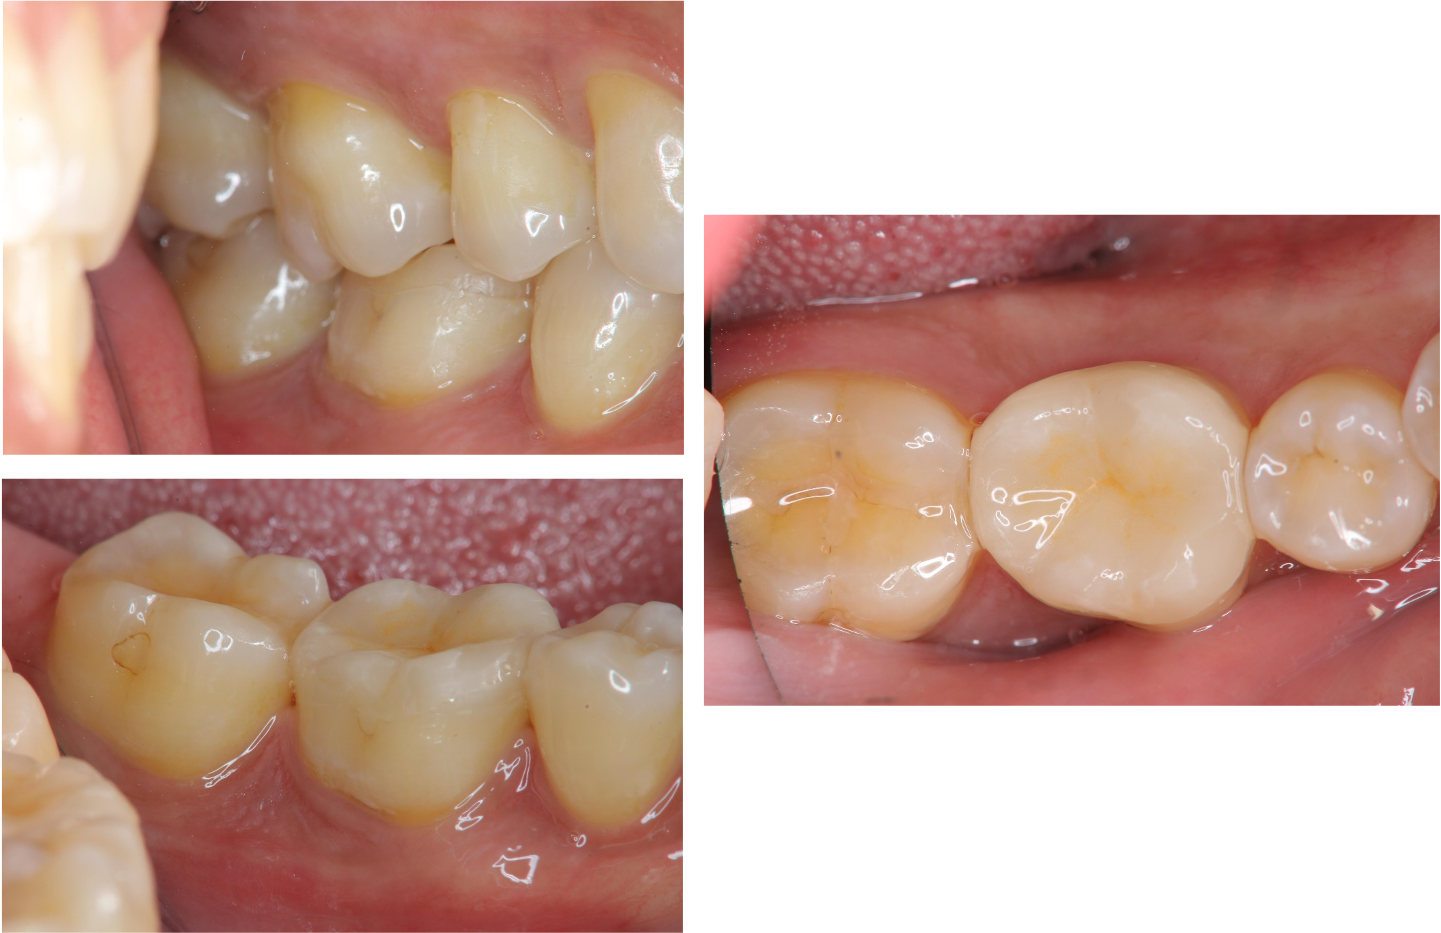

治療前,牙齒破損與蛀牙

治療前,蛀牙與根尖破壞

雷射切除牙齦,冠塊體製備

冠塊體黏著

治療後口內照